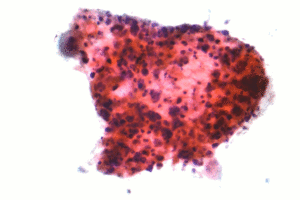

| Micrograph of a squamous carcinoma, a type of non-small-cell lung carcinoma. FNA specimen. Pap stain. | |

Squamous cell lung carcinoma

Squamous cell carcinoma (SCC) of the lung is more common in men than in women. It is closely correlated with a history of tobacco smoking, more so than most other types of lung cancer. According to the Nurses' Health Study, the relative risk of SCC is approximately 5.5, both among those with a previous duration of smoking of 1 to 20 years, and those with 20 to 30 years, compared to never-smokers.[11] The relative risk increases to approximately 16 with a previous smoking duration of 30 to 40 years, and approximately 22 with more than 40 years.[11]